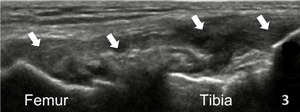

In the LAX view, depending on the probe width and size, one should start distally to visualize the hyperechoic reflection of the bony cortex of the fibular head distally and the cortex of the femoral epicondyle more proximally. If the depth is increased enough, you will also be able to visualize the bony reflection of the tibia directly below the fibular head. Usually, the LCL demonstrates a hyperechoic fibrillar pattern. The distal portion of the tendon may appear heterogeneous and thickened due to the bifurcating distal biceps femoris tendon that runs both superficial and deep to the LCL.9